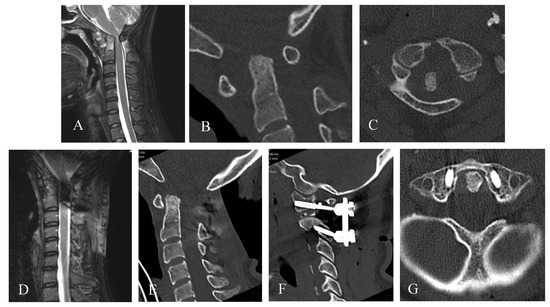

Illustrative Case (2)

| Cervical pathology | AAI, retrodental pannus | AAS | AAI, retrodental pannus | CS | AAI, retrodental pannus, cervical spinal stenosis subaxial | AAI, retrodental pannus | AAS, retrodental pannus | CS | CS |

| Symptoms | neck pain, ataxia, hemiparesie, not able to walk | fine motor disorders, monoparesis, bladder emptying disorders, ataxia | monoparesis | tertaparesis, not able to walk, dysphagia, loss of warm cold discrimination of the legs | monoparesie, ataxie | neck pain, ataxie | ataxie, sensory deficit | dysphagia, tetraparesie, not able to walk | ataxie, dysphagia, sensory deficit |

| Surgery | 1. posterior fixation C1-3 + laminectomy C1-2 2. transnasal endoscopic dens resection | closed reduction, osterior fixation C1-2 | posterior fixation C1-2, laminectomy C1 | posterior fixation C0-2-3-4 | posterior fixation C1-2-4-6 + laminectomy C1-6 | posterior fixation C1-2 | posterior fixation C1-2 | posterior fixation C0-3-4, laminectomy C1, decompression suboccipital | 1. posterior fixation C0-2, decompression suboccipital 2. transnasal endoscopic resection of dens and clivus (21 months later) |

| Complications | temporary hemiplegie postoperatively | no | no | deceased | No | no | no | no | no |

| Follow up | after 8 months, improvement of hemipaesis, walking possible with aide | after 12 months, no symptoms | no follow up | no follow up | no follow up | no follow up | 11 months | after 3 months, walking possible | after 5 years |

| Post-operative mJOA score | 12 | 17 | 15 | deceased | 15 | 16 | 16 | 12 | 16 |